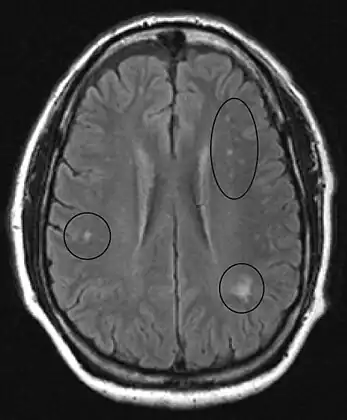

MRI of the brain may show periventricular white matter abnormalities. MRI of the spinal cord may show linear hyperintensity in the posterior portion of the cervical tract of the spinal cord, with selective involvement of the posterior columns.

MRI image of the brain in vitamin B12 deficiency, axial view showing the "precontrast FLAIR image": note the abnormal lesions (circled) in the periventricular area suggesting white matter pathology.